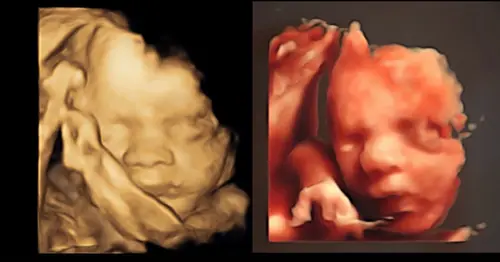

Wij weten het geslacht niet, maar willen wel graag een 3d echo. Kan dat gewoon? Hoe gaat het in zijn werk?

7 maanden geleden

Reactie op FlexibeleRegendruppel113882

Wij weten het geslacht niet, maar willen wel graag een 3d echo. Kan dat gew ...

ja hoor. gewoon aangeven, ik heb in 3/4D alleen haar gezichtje gezien